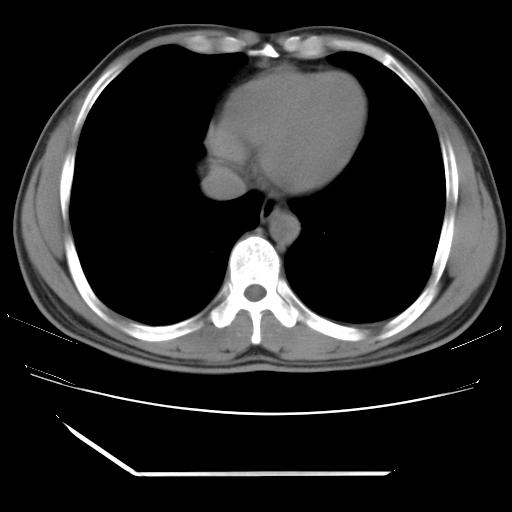

男,38岁,于2009年8月9日晚突发左侧胸痛,今x线提示左下肺阴影,为了明显确诊断,行ct检查,

血常规:嗜酸性细胞增高,单核细胞增高。

纵膈窗

病灶发生在下叶,密度均匀,边缘模糊、毛糙,周围血管纹理增强扭曲改变,靠近胸膜处病灶胸膜反应明显。

支持考虑---球形肺炎。

左肺舌叶病变。主体病灶呈类圆形中心密度低,成液化趋势周边班片影分布

考虑肺脓肿

虽然实验室检查支持炎性病变,且病变内有坏死改变(中央呈大片状低密度影),但仍不能掉以轻心,鳞癌也可以有这种影像改变。